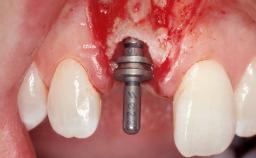

| Type of Implants | One-Piece|Reduced-Diameter |

| Attachment | One-Piece|Reduced-Diameter |

| Bone Augmentation | Horizontal|Staged |

| Augmentation Materials | Autogenous chips|Membrane |